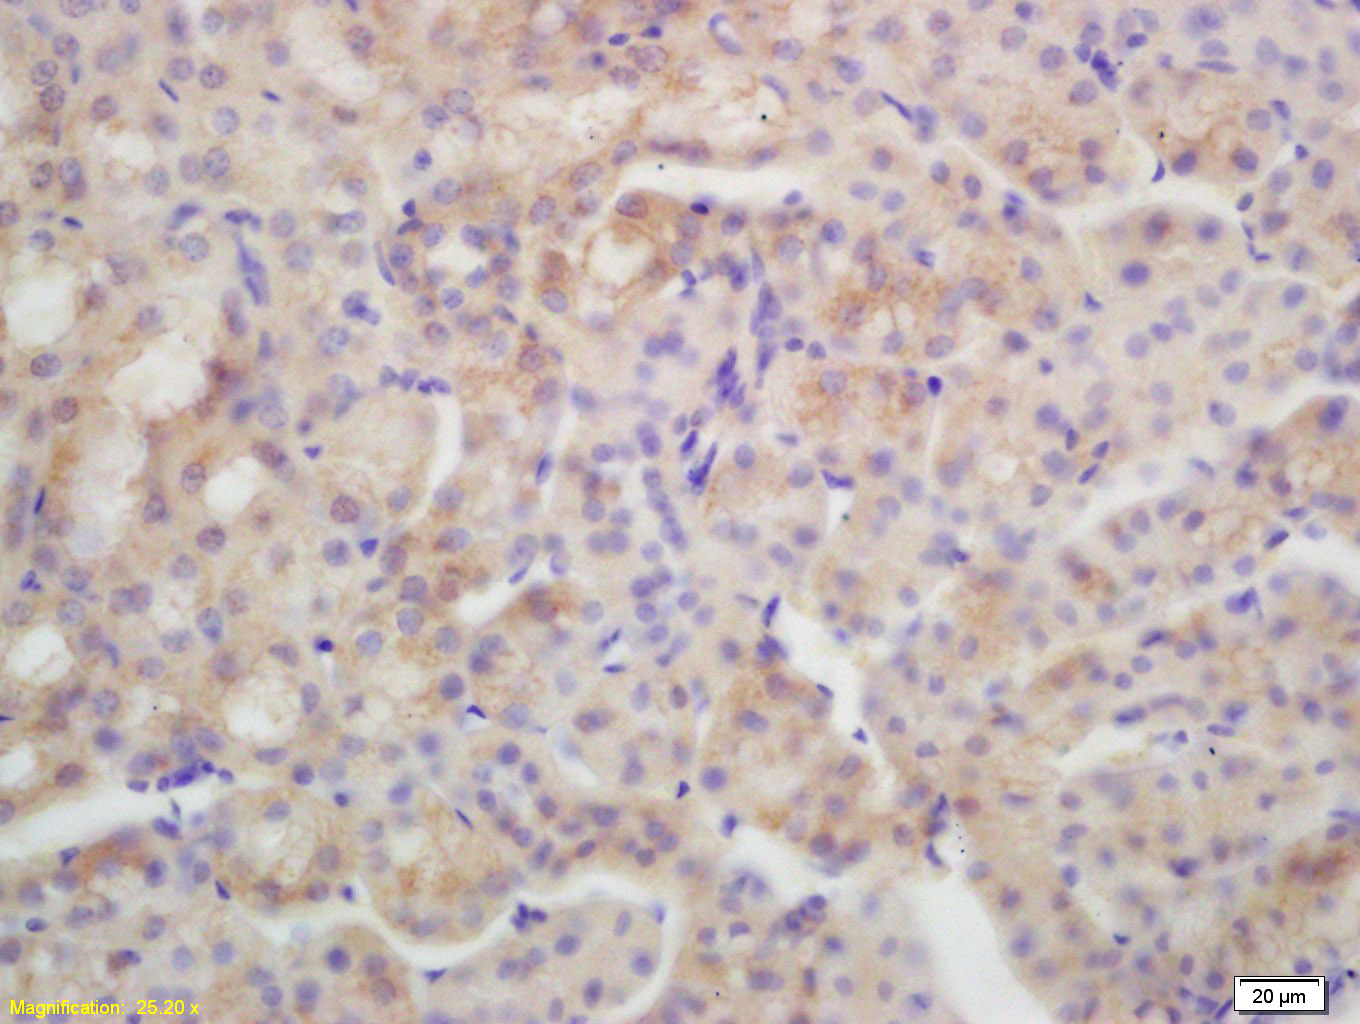

| IHC-P | Human, Mouse, Rat | Rabbit, Pig, Sheep, Cow | 1:100-500 |